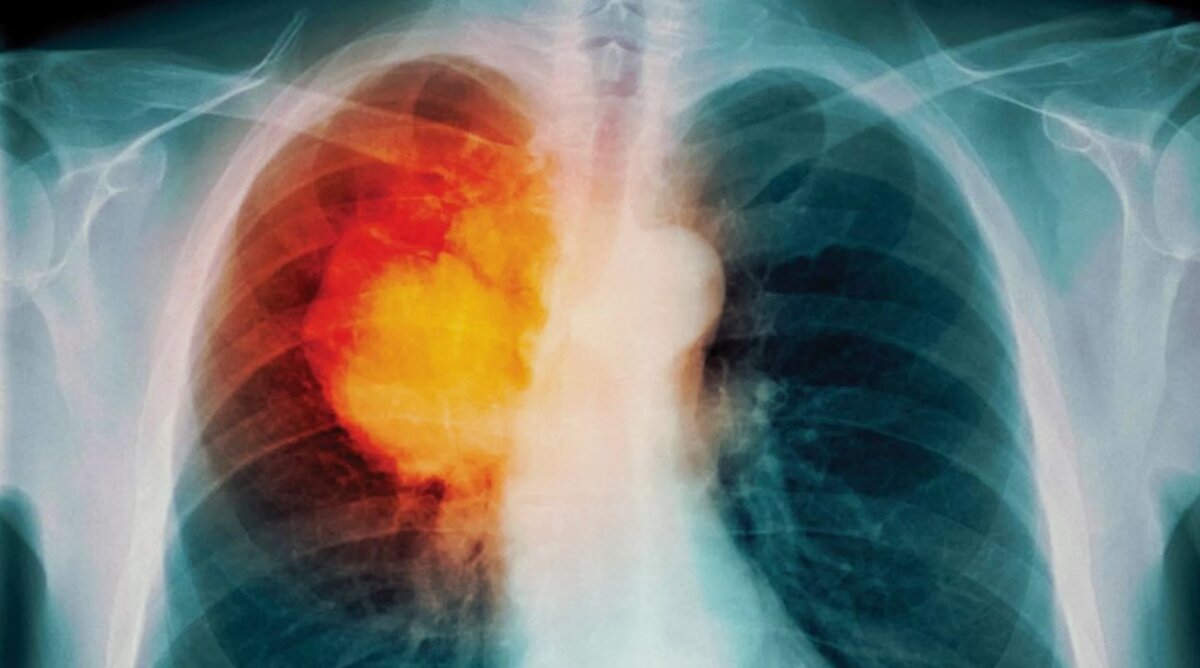

Рак легких занимает второе место среди причин смертей во всем мире

– заболеваемость этими заболеваниями 6% сконцентрирована в возрастных группах 50 лет и младше, 21% охвачена возрастными группами от 50 до 60 лет, 29% в возрасте от 60 до 69 лет и 44% среди пациентов 70 лет и старше. Возраст во многом определяет уровень смертности от болезней легких, – самые высокие показатели смертности были обнаружены в пожилом возрасте независимо от пола. Рак легких занимает второе место среди причин смертей во всем мире, сопровождаемых раком молочной железы у женщин, по разным оценкам, 2,2 миллиона новых случаев и 1,8 млн смертей в 2020 г. В США менее 0,5% смертей возникают из-за рака легких среди молодых людей в возрасте до 40 лет, и этот уровень заболеваемости резко возрастает примерно в возрасте 45–49 лет и достигает пика в возрастной группе 85–89 лет для мужчин и 80–84 лет для женщин (более 70%);